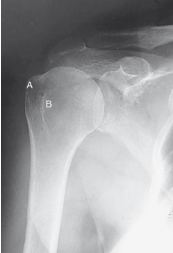

label the anatomy accordingly A-G, the projection/part, and rotation if applicable

head of humerus, greater tubercle, intertubercular sulcus, lesser tubercle, anatomic neck, surgical neck, body

AP shoulder — external rotation